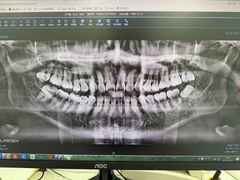

• 欢乐口腔(望京分院)

• -欢乐口腔(望京分院)